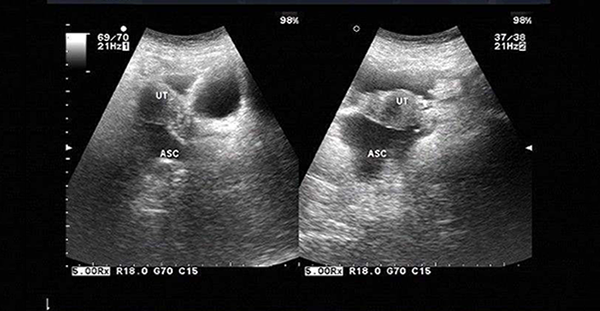

B超检查下的盆腔积液